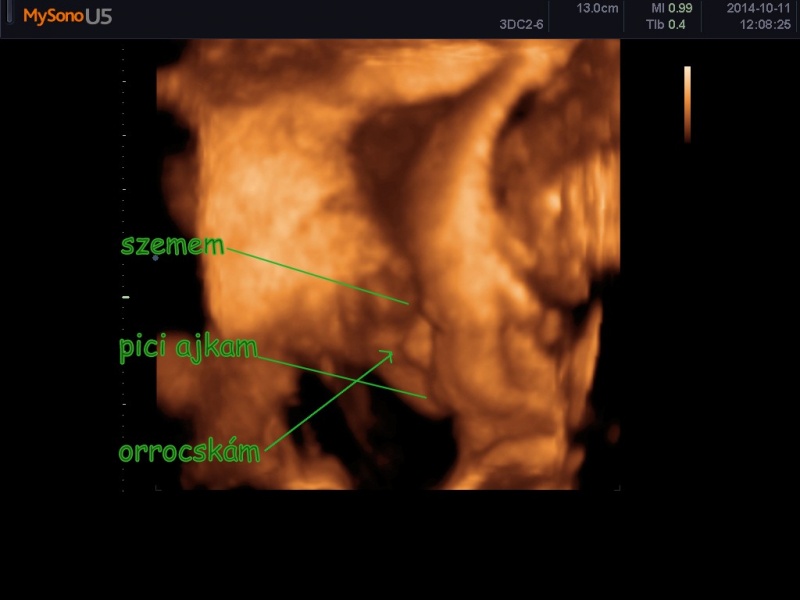

Nálunk minden rendben van ![]() ma voltunk uh-n

ma voltunk uh-n ![]() képeket fel is teszem

képeket fel is teszem ![]()

Őszinte leszek azt, hittem többet fog megmutatni magától , de tévedtem ![]()

De örülök neki, hogy jól van ![]() jah és 785grammos a centit nem tudjuk , mert össze volt gömbölyödve angyalom